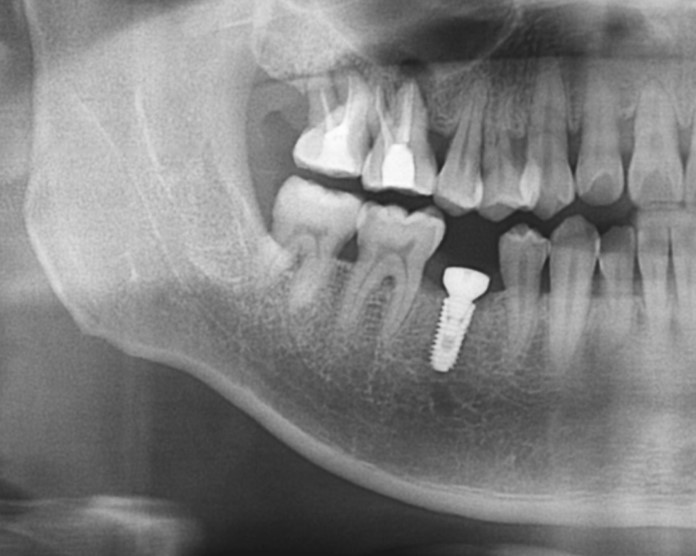

▲Radiograph after impant surgery.